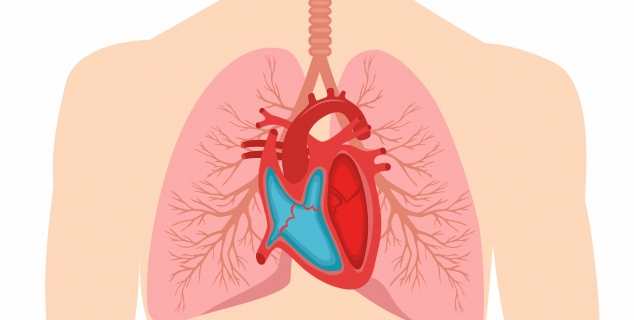

Hjertet og lungene // اقلب والرئتان

Dette kan brukes som en introduksjon hvor elevene kan lære om hvordan hjertet fungerer og hvordan blodet transporterer næring og oksygen ut til kroppen. Opplegget består av tekst og kan passe for mellomtrinnet.